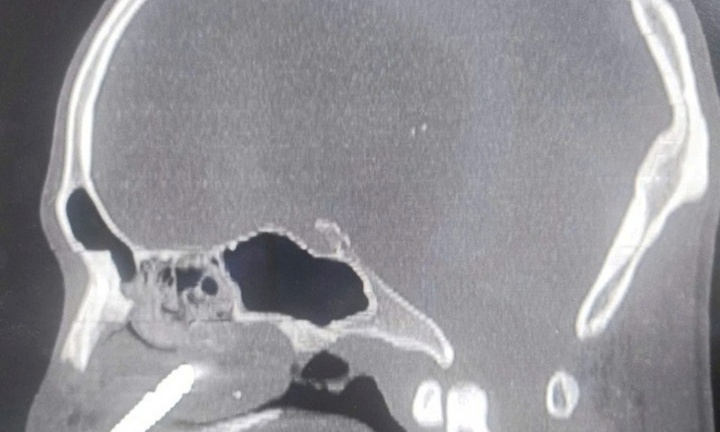

Mũi khoan đá bất ngờ bật ra, đâm vào hốc mũi của anh Lê, 27 tuổi, khiến anh bị mất nhiều máu và rơi vào tình trạng nguy kịch.